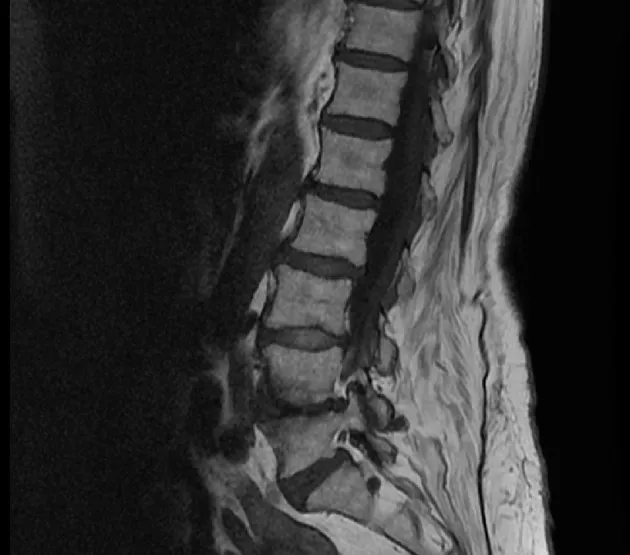

Typisch für unspezifische Rückenschmerzen ist, dass oft keine strukturellen Ursachen erkennbar sind. Diese Ungewissheit führt häufig zu einer Verunsicherung bei den Betroffenen. In der Hoffnung, eine Ursache zu finden, werden dann bildgebende Untersuchungen wie Magnetresonanztomografie (MRT) oder Röntgen durchgeführt, die dann häufig alters- oder verschleißbedingte Veränderungen zeigen. Diese radiologischen Befunde haben jedoch oft keinen realen Bezug zu den empfundenen Schmerzen.

Strukturelle Veränderungen an der Wirbelsäule sind auch bei einem erheblichen Anteil der beschwerdefreien Bevölkerung nachweisbar. So zeigen etwa 37 % der 20-Jährigen, die keine Rückenschmerzen haben, bereits degenerative Veränderungen im Bereich der Bandscheiben. Bei Personen über 40 steigt dieser Anteil deutlich an: Mehr als die Hälfte weist Anzeichen einer „Black Disc“ auf, bei den über 60-Jährigen sind es sogar über 85 % (Brinjikji et al., 2014). Solche Veränderungen gehören also zum normalen Alterungsprozess des Körpers.

Die Diskrepanz zwischen dem, was auf dem Bild zu sehen ist, und dem, was empfunden wird, ist groß – und hier liegt eine Herausforderung in der Kommunikation. Wird etwa ein MRT-Befund vom Patienten als dauerhafte „Schädigung“ interpretiert, kann dies Ängste auslösen, das Vertrauen in die eigene Belastbarkeit untergraben und letztlich zu einer Reduktion körperlicher Aktivität führen.

Ein struktureller Aspekt, der bei der Beurteilung anhaltender Rückenschmerzen an Bedeutung gewinnt, ist die sogenannte Fettinfiltration der Rückenmuskulatur insbesondere im Bereich der Lendenwirbelsäule (L3–L5) (Abb. 1). Hierbei handelt es sich nicht um ein direktes Verschleißphänomen, sondern um die Einlagerung von Fettgewebe innerhalb der Muskulatur. Sie lässt sich mittels MRT sichtbar machen und wird als Marker für muskuläre Inaktivität interpretiert. Die intramuskuläre Verfettung tritt häufiger bei Menschen mit anhaltenden Rückenbeschwerden auf und gilt als Hinweis auf eine verminderte funktionelle Kapazität der stabilisierenden Rumpfmuskulatur. Der erhöhte Fettanteil kann die Kontraktionsfähigkeit einschränken, die neuromuskuläre Kontrolle und die Funktion der Wirbelsäule beeinträchtigen. Er lässt sich nicht allein durch eine allgemeine Gewichtsreduktion beeinflussen; auch Ausdauertraining hat nur einen begrenzten Effekt. Wirksamer ist der gezielte Aufbau funktioneller Muskelmasse insbesondere durch spezifisches Krafttraining der Rumpfmuskulatur. Gezieltes freies Krafttraining über einen Zeitraum von mehreren Wochen unter Einbezug funktioneller Grundübungen wie Kniebeugen kann nachweislich zu einer Reduktion der Fettinfiltration in der Rückenmuskulatur beitragen. Gleichzeitig lassen sich so positive Effekte auf die Ausdauer sowie auf die funktionelle Leistungsfähigkeit der Muskulatur beobachten (Welch et al., 2015).